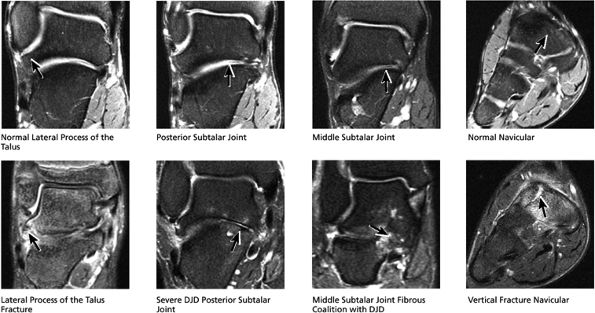

|

FIGURE 5.41 Subtalar Joint.